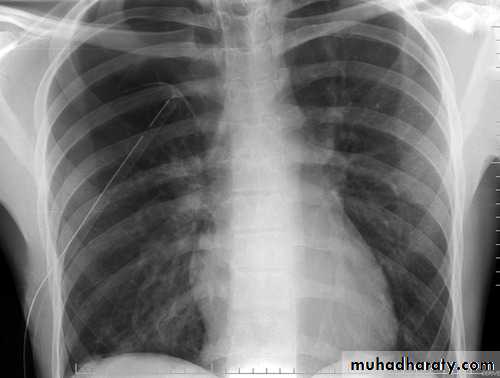

Severe dyspnea with shock